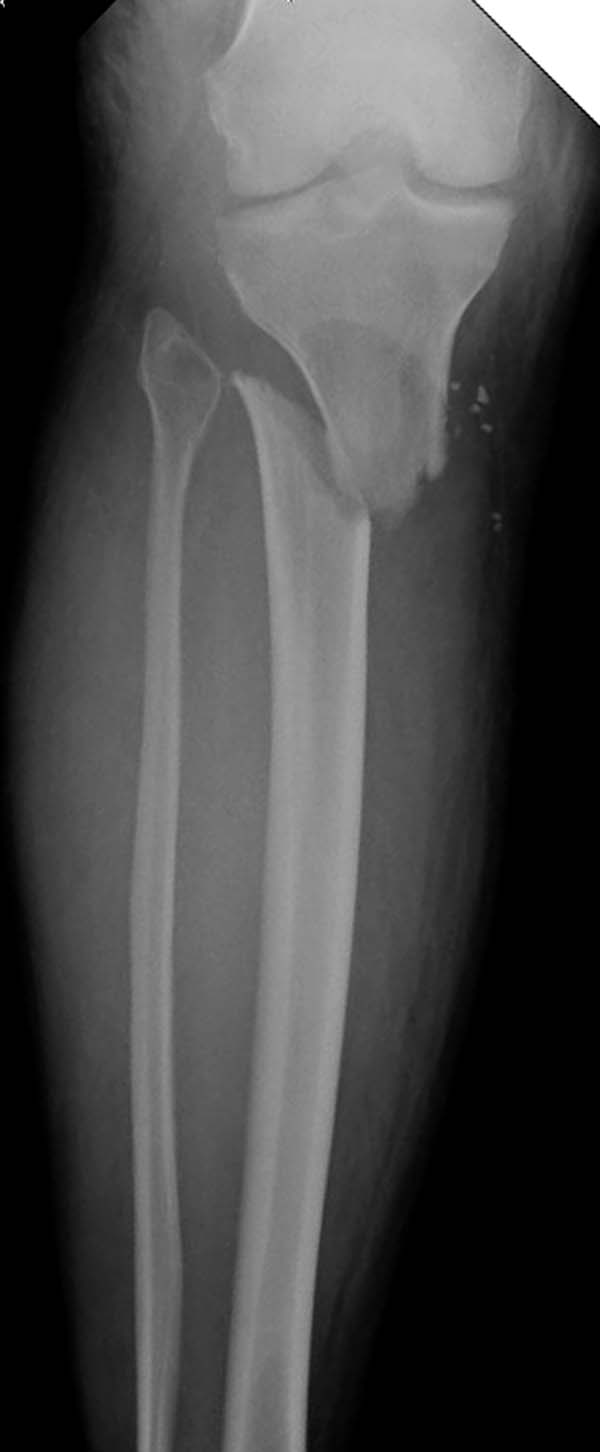

Здесь, кроме перелома верхней трети голени, имеется вовлечение сустава, и, чтобы не пропустить смещение суставной поверхности, надо делать КТ. Срезы КТ покажут о необходимости субхондральной фиксации, которая проводится 3.5 мм параллельными шурупами (Raft technique). Не имеет значения, как проводить: отдельно субхондрально или через верхний ряд пластины. Главная задача фиксации удержать суставную поверхность от коллапса в вальгус или варус.

Здесь случай, так называемого floating knee перелома выше и ниже коленного сустава.

здравствуйте! создается впечатление о фиксации перелома голени в варусном положении

Согласен, на снимке “создается впечатление о фиксации перелома голени в варусном положении”, но на других отсутствует..